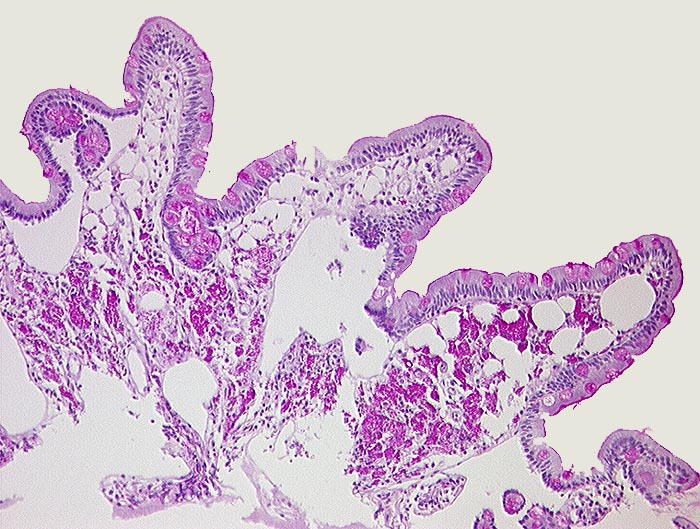

AP/ Morbus Whipple

Morbus Whipple

Dünndarm

Pathologischer Befund